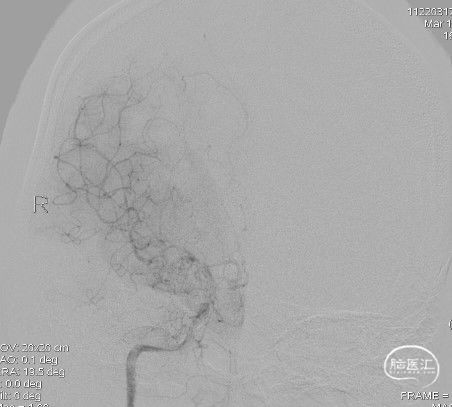

右侧颈内动脉侧位:

造影:右侧颈内动脉末段变细,右侧大脑中动脉M1段分叉前重度狭窄,豆纹动脉增多,右侧大脑前动脉向大脑中动脉分布区代偿供血:

三维重建显示右侧大脑中动脉分叉前部重度狭窄,狭窄段直径0.4mm,狭窄程度约84%: